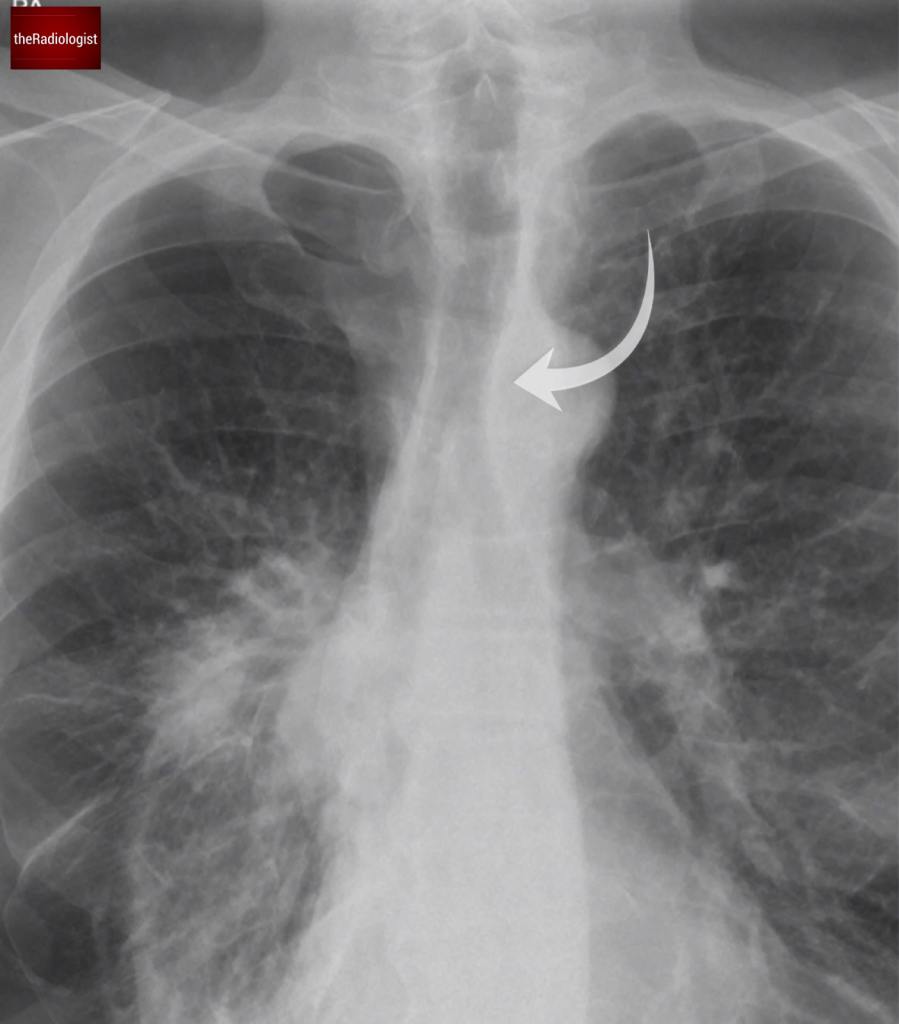

Once we see a pneumothorax on X-Ray, how do we assess for tension?

1. Mediastinal shift: for a clue I always check to see if some of the heart is to the right of the spine (as long as the film is not rotated). Look at the position of the trachea. If you are unsure about mediastinal shift comparing to old films can help you.

2. Flattening of the diaphragm

Remember that tension is unlikely to happen with small apical pneumothoraces.

Now if we look at our case we can see the trachea and mediastinum are central meaning there is no tension pneumothorax.

In our case the trachea is in a normal position with no signs of shift to suggest shift in the context of tension. Note minor deviation of the trachea to the right at the level of the aortic arch is normal.

Assessing for lung lesions

There isn’t just a pneumothorax in this case, the underlying lung looks abnormal. Looking closely we can see a right mid zone opacity and a second opacity behind the right hilum (see the image below).

Look closely and you will find two opacities within the right mid zone, one within the right mid zone and another overlying the right hilum.